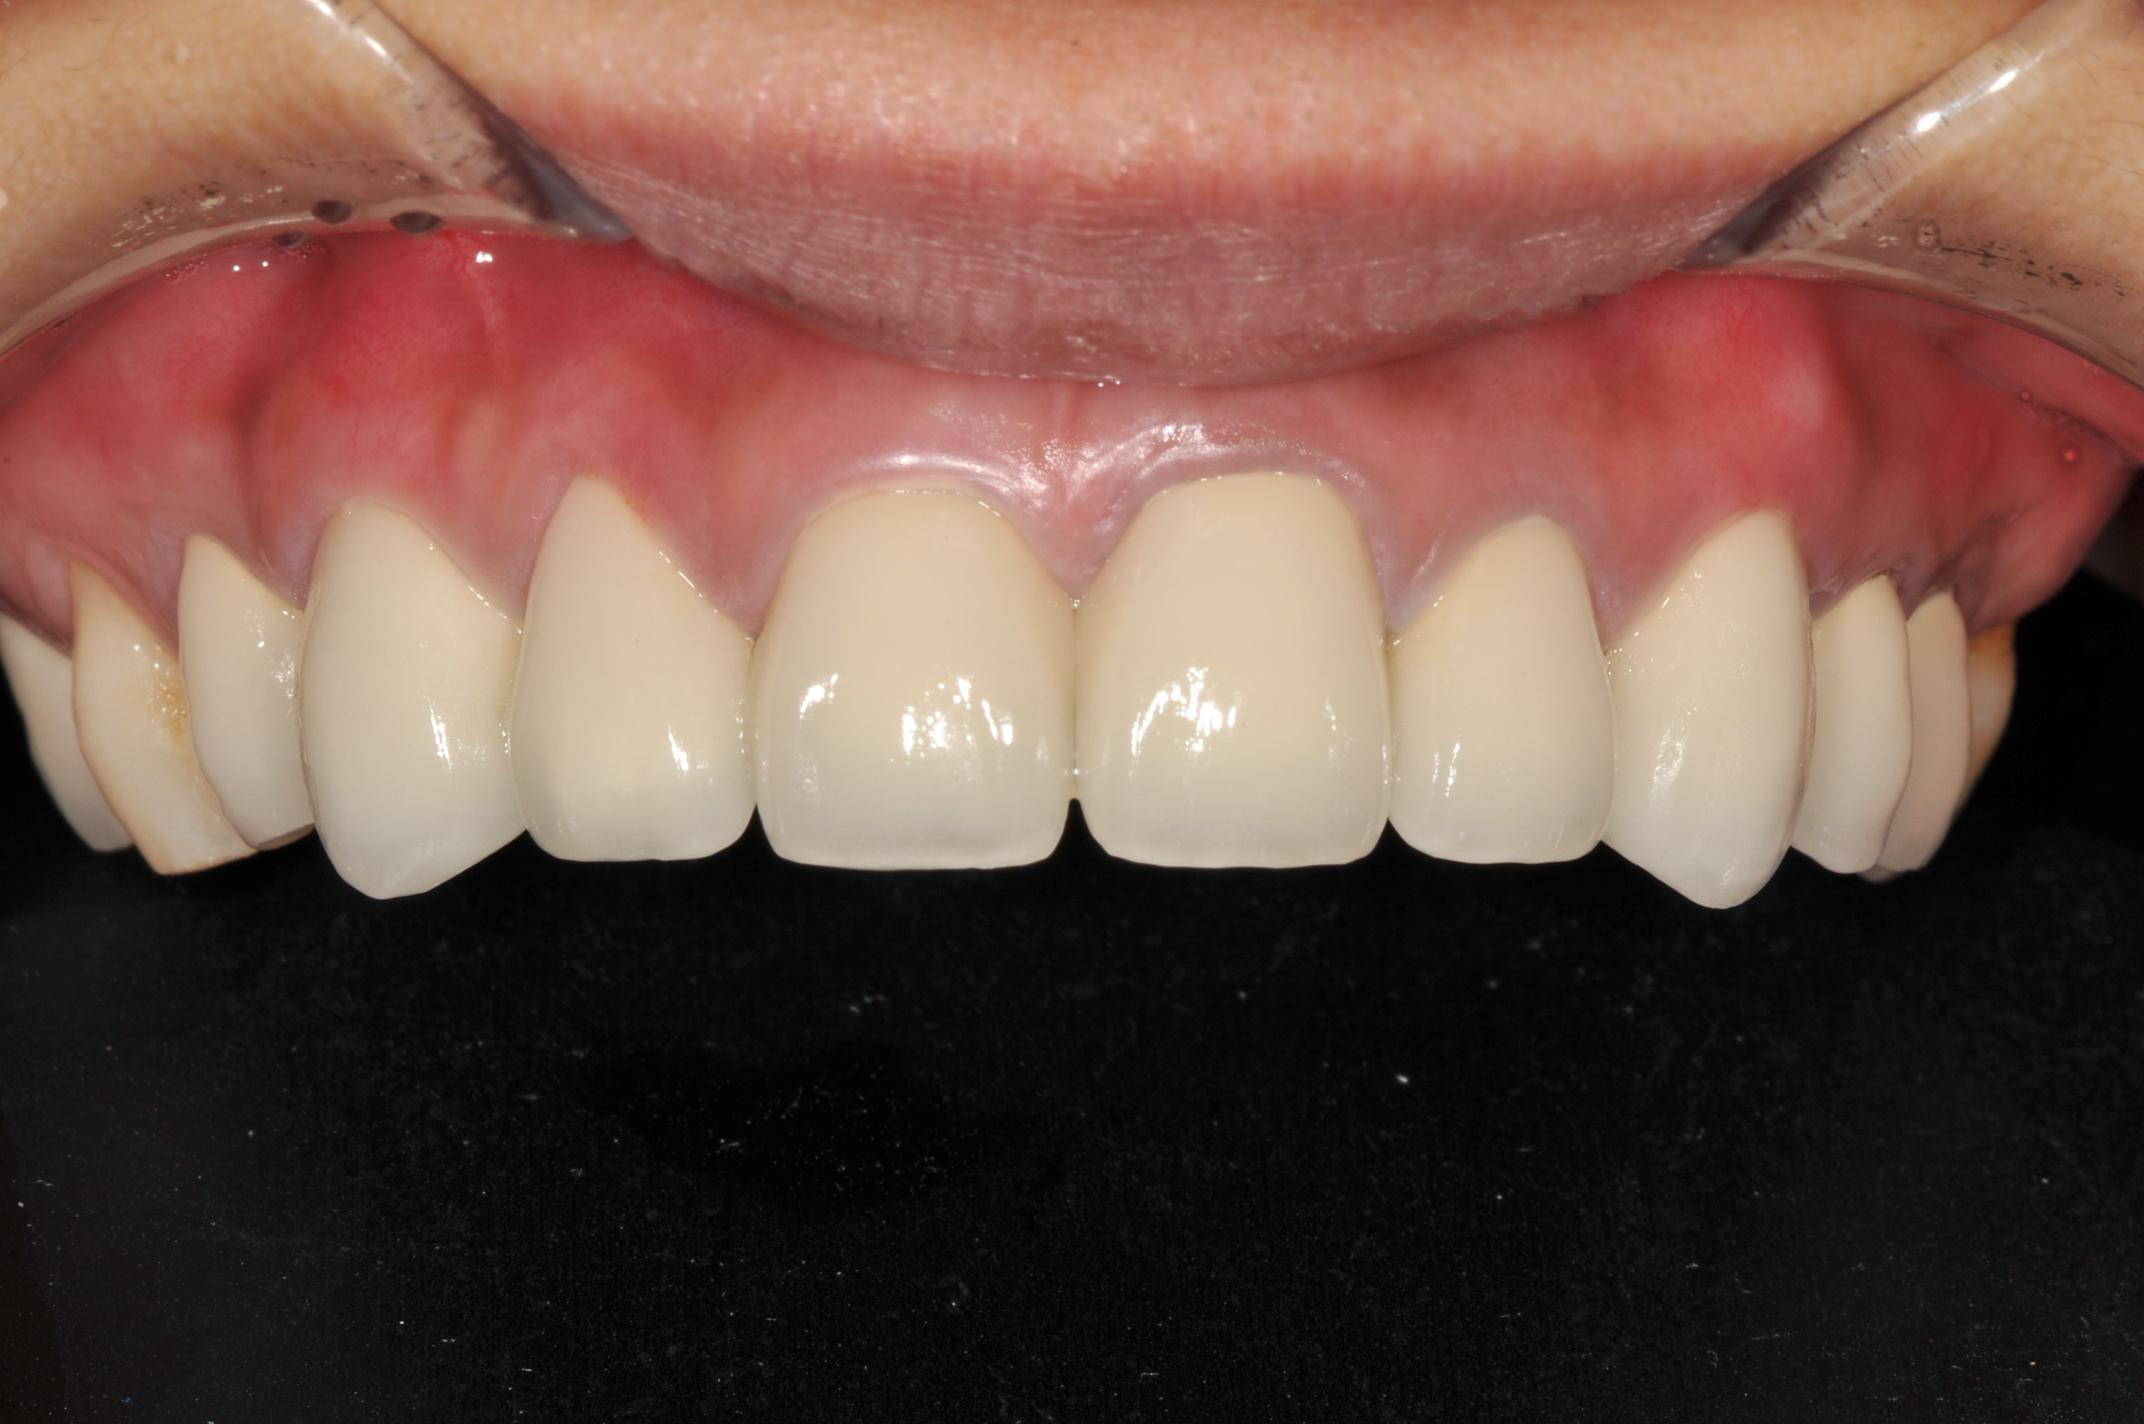

四、以臨時假牙模擬未來假牙外型(圖四)

圖四 |

五、下頷牙齒居家美白(圖五、圖六)

圖五(下頷美白前) |

圖六(下頷美白後) |

六、假牙印模及製作(圖八)及數位比色(圖七)

由於是前牙,本院採用Cynovad數位比色機比色(圖七),並以高階數位單眼相機記錄牙齒的表面紋路及局部色澤(染色、斑點等),因此技師即使未親臨現埸,仍可得到最精準的比色資料。